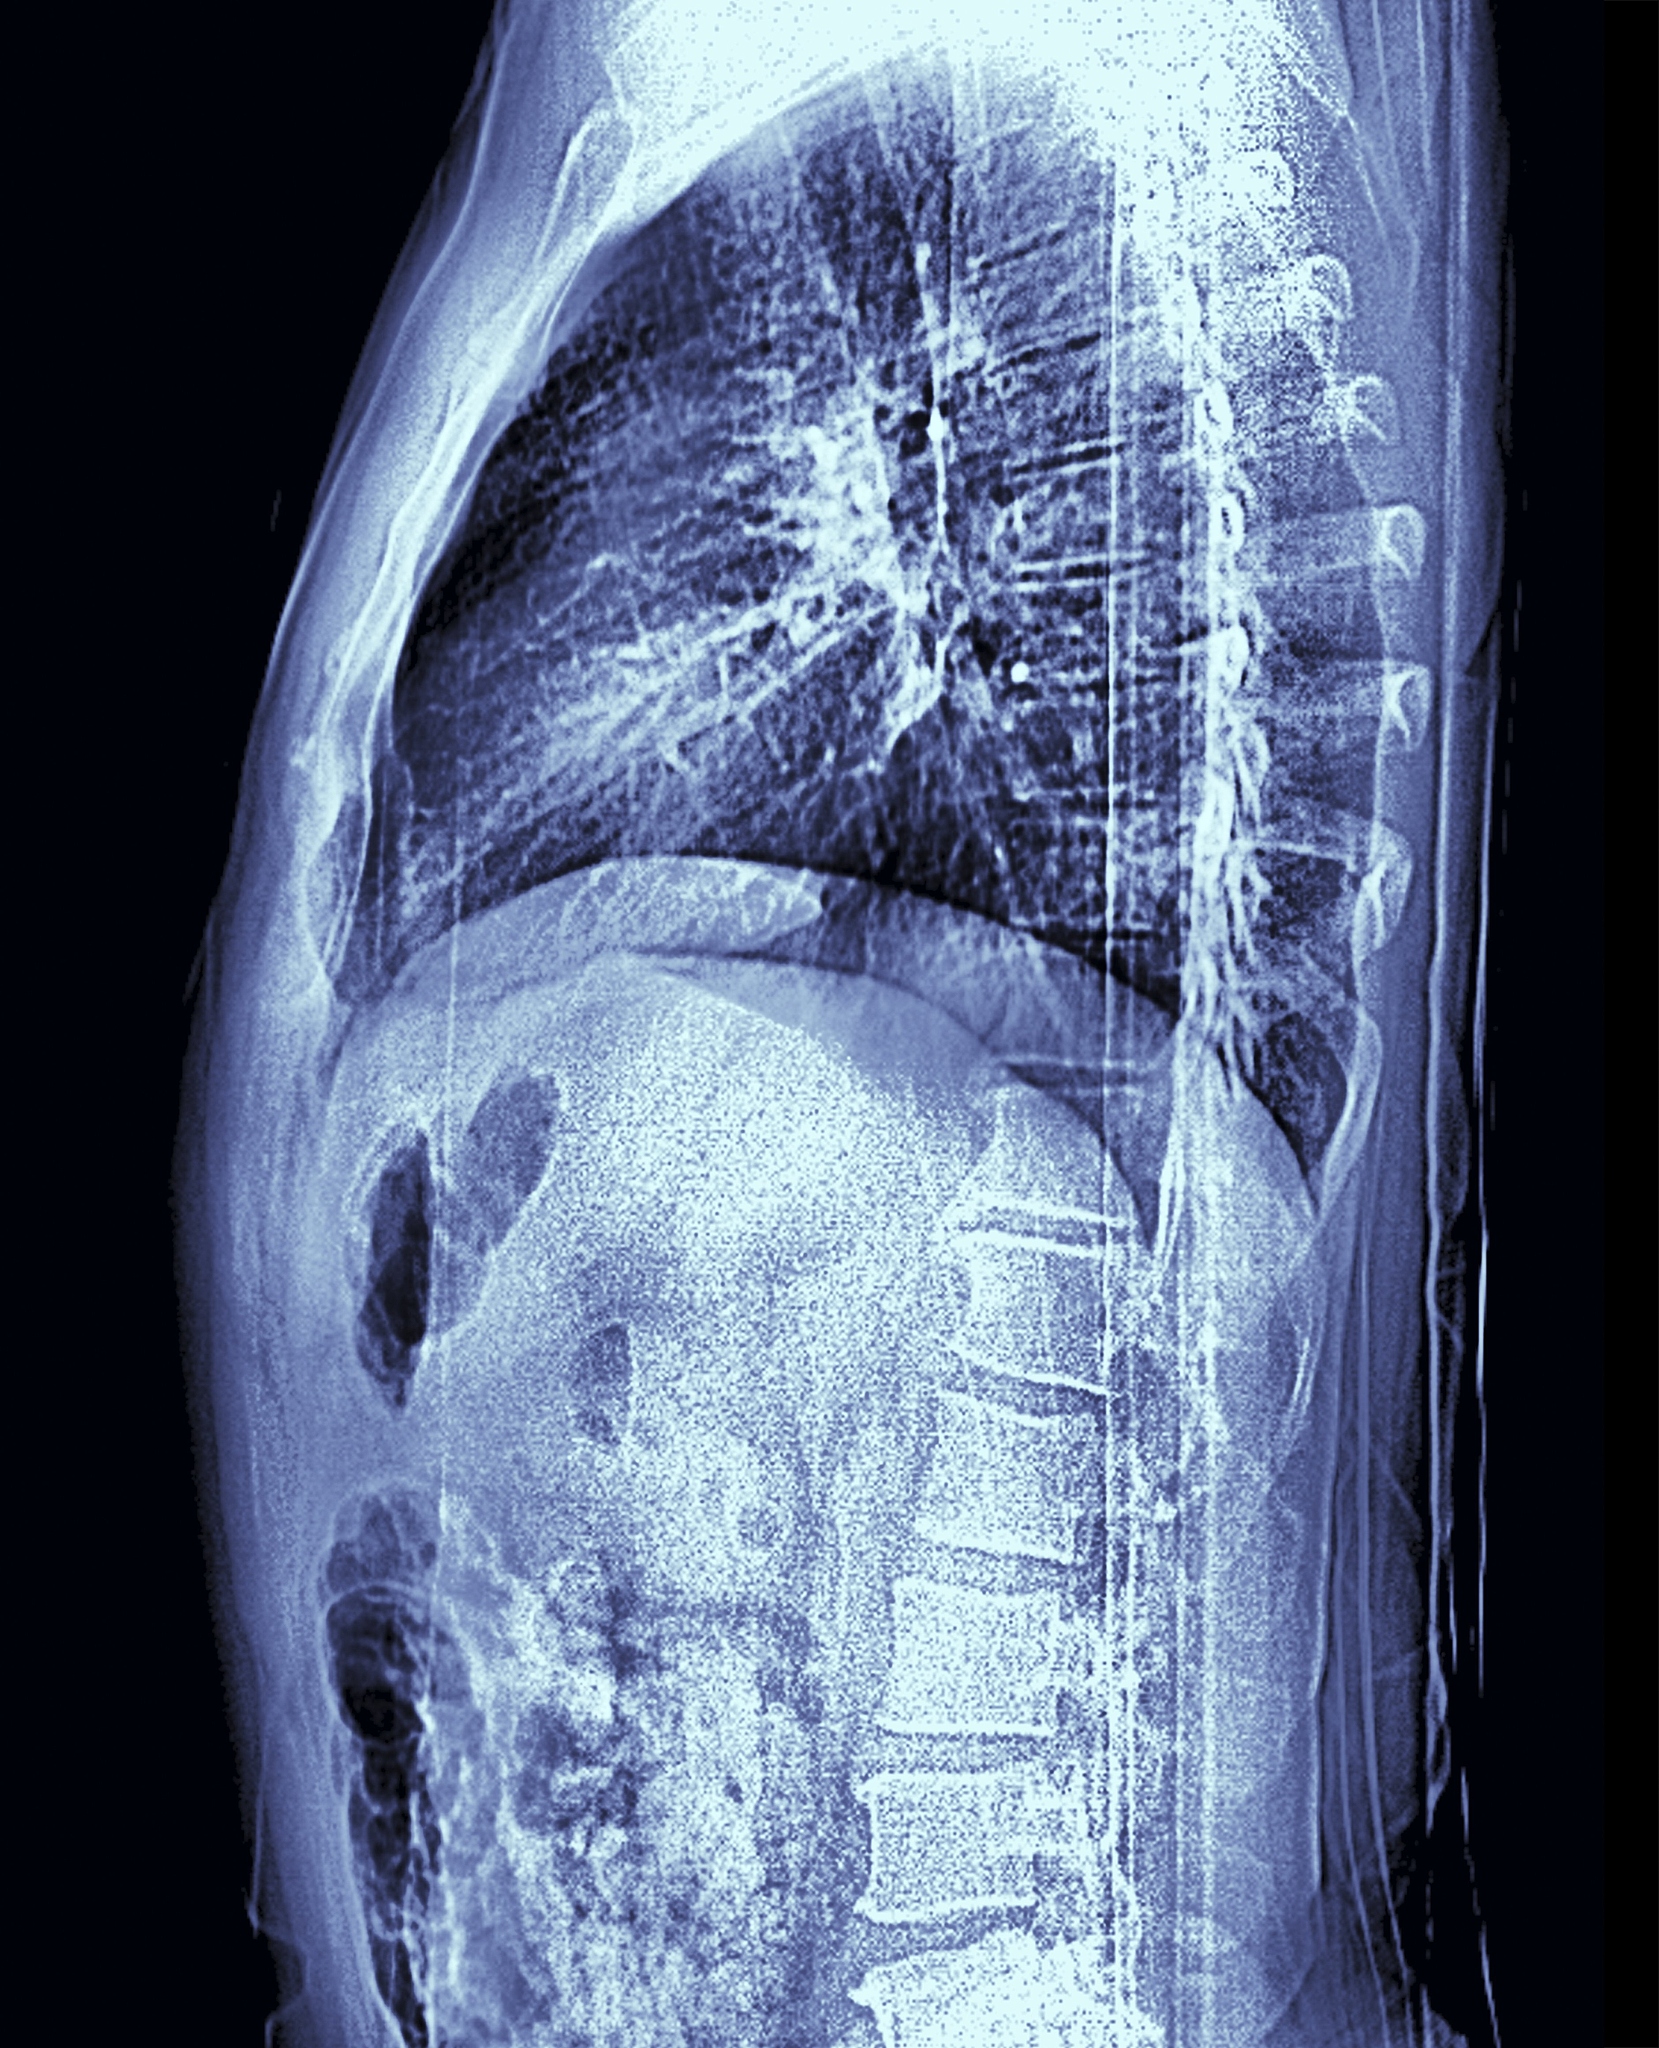

3. "Soft Tissue Sarcomas: Imaging Features, Histopathologic Correlation, and Imaging-Based Treatment Assessment" by A. Buehler et al. published in Radiographics in 2018. This article reviewed the utility of MRI and CT in soft tissue sarcoma diagnosis and treatment planning.

5. "Soft Tissue Sarcomas: Imaging Evaluation with Emphasis on MRI" by P. M. Parikh et al. published in Journal of Clinical Imaging Science in 2013. This article discussed the role of MRI in the diagnosis and management of soft tissue sarcomas.

7. "Soft Tissue Sarcomas: Diagnostic Imaging Approach" by C. J. H. van Rijswijk et al. published in Cancer Imaging in 2012. This article discussed the diagnostic imaging approach to soft tissue sarcomas, including the use of CT and MRI.

9. "Soft Tissue Sarcomas: An Imaging Review" by A. D. Levy et al. published in Clinical Imaging in 2001. This article provided an overview of the imaging features of soft tissue sarcomas, including the appearance of calcifications and fat on CT and MRI.

综述以上文献,软组织肉瘤在CT和MRI上呈现为软组织肿块,具有良恶性不同的表现特征。MRI比CT更适用于软组织肉瘤的检测和诊断,CT可检测到钙化和脂肪。增强CT和MRI对于鉴别良恶性肿瘤以及治疗方案制定具有重要意义。新兴的诊断成像技术如扩散加权MRI和PET-CT也在软组织肉瘤的诊断中得到应用和研究。